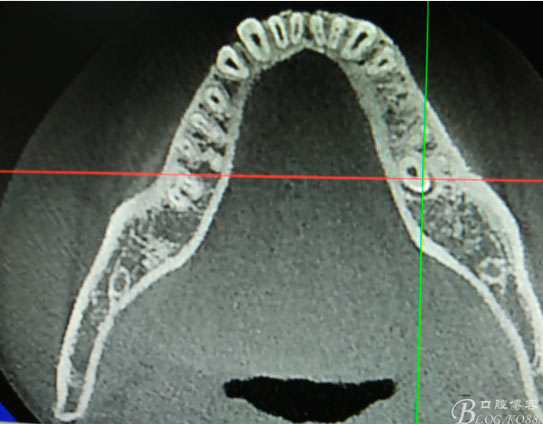

患者、盧xx、男、19歲。主訴:左側下頜乳磨牙未脫落,要求檢查。??茩z查:左側下頜第二乳磨牙有充填物。無松動,全景片檢查。35移位至36、37之間。頰舌側均不能觸及隆起。CBCT檢查:35位于36、37的舌側。表面骨質約2mm左右。35完全骨埋伏,36的遠中牙根疑是吸收。建議35暫觀察。置留不取。患者要求拔除擔心壓迫36牙根或者發(fā)生囊性變。術前簽手術同意書。

圖1.術前的全景片影像檢查,35移位至36、37之間。